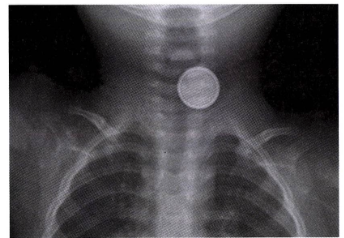

식도 이물 (Esophageal Foreign Body)

• 개요: 소아에서 흔하며, 동전, 장난감, 건전지 등이 주된 물질

• 임상 양상

• 사래, 구역,과도한 침흘림, 삼킴곤란, 통증, 기침.

• 날카로운 이물은 식도 천공, 누공 등 심각한 합병증 유발 가능

• 수은 건전지는 부식성 손상, 전기화상, 압력손상 유발. 4시간 이내 식도 전층의 화상 유발 가능

• 진단: 병력 청취 및 X-ray

• 수은 건전지는 X-ray에서 이중테두리(double-halo) 징후를 보임

• 치료: 내시경 제거가 원칙

• 수은 건전지: 금식 여부와 관계 없이 2시간 이내에 응급 내시경을 통한 제거

• 날카로운 물체 또는 호흡기증상 있음: 12시간 이내 제거

• 동전, 뭉툭한 물체: 금식시간을 확보한 후 24시간 안에 제거